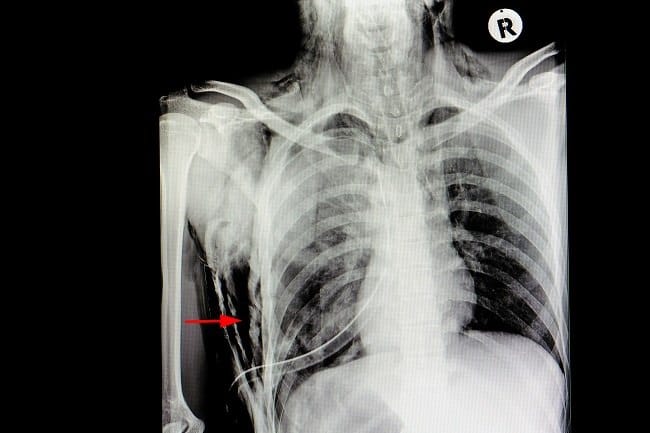

- Foto Rontgen dada, untuk mendeteksi udara yang terperangkap di dalam rongga dada dan perut